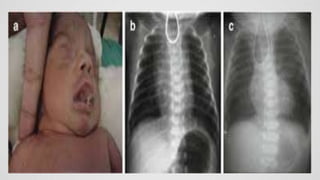

The simplest test for TEF is to gently attempt to place a 10F

(french replogle tube) or larger tube via the mouth into the

stomach. The passage

of the tube is blocked at the level of the atresia. A chest x-

ray: reveals the tube coiled in the esophageal pouch. Air

can be injected through the tube to outline the atretic

pouch.

Demonstration of the nasogastric tube curled in the proximal

oesophagus in a child where the passage of the tube has been

unsuccessful is usually sufficient for diagnosis. The proximal

oesophageal stump may be distended with air (types A and C).

The presence of air in the stomach and bowel in the setting of

oesophageal atresia implies that there is a distal fistula.

Often the lungs demonstrate areas of consolidation/atelectasis

due to recurrent aspiration.